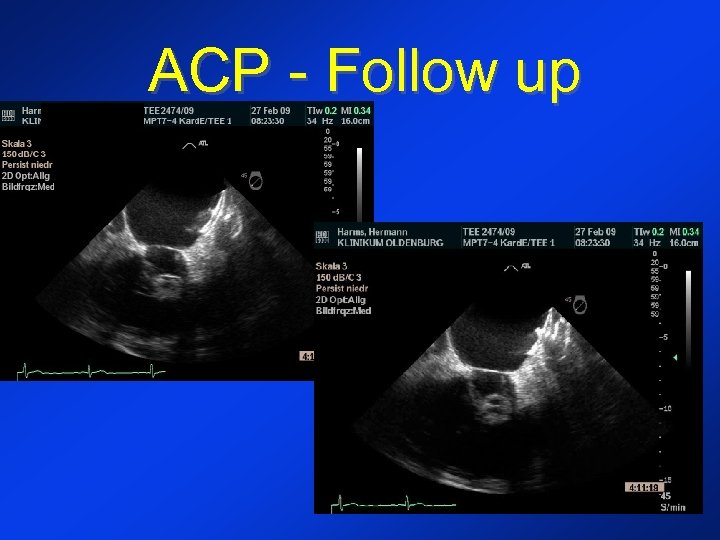

ACP - Follow up